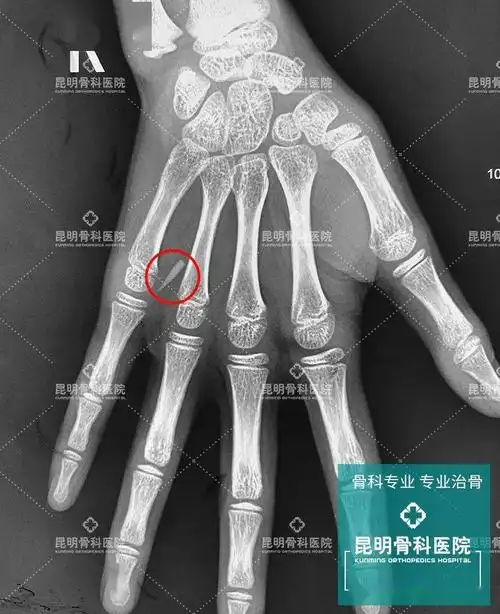

9岁女孩手掌刺痛,x光下拍到惊人一幕